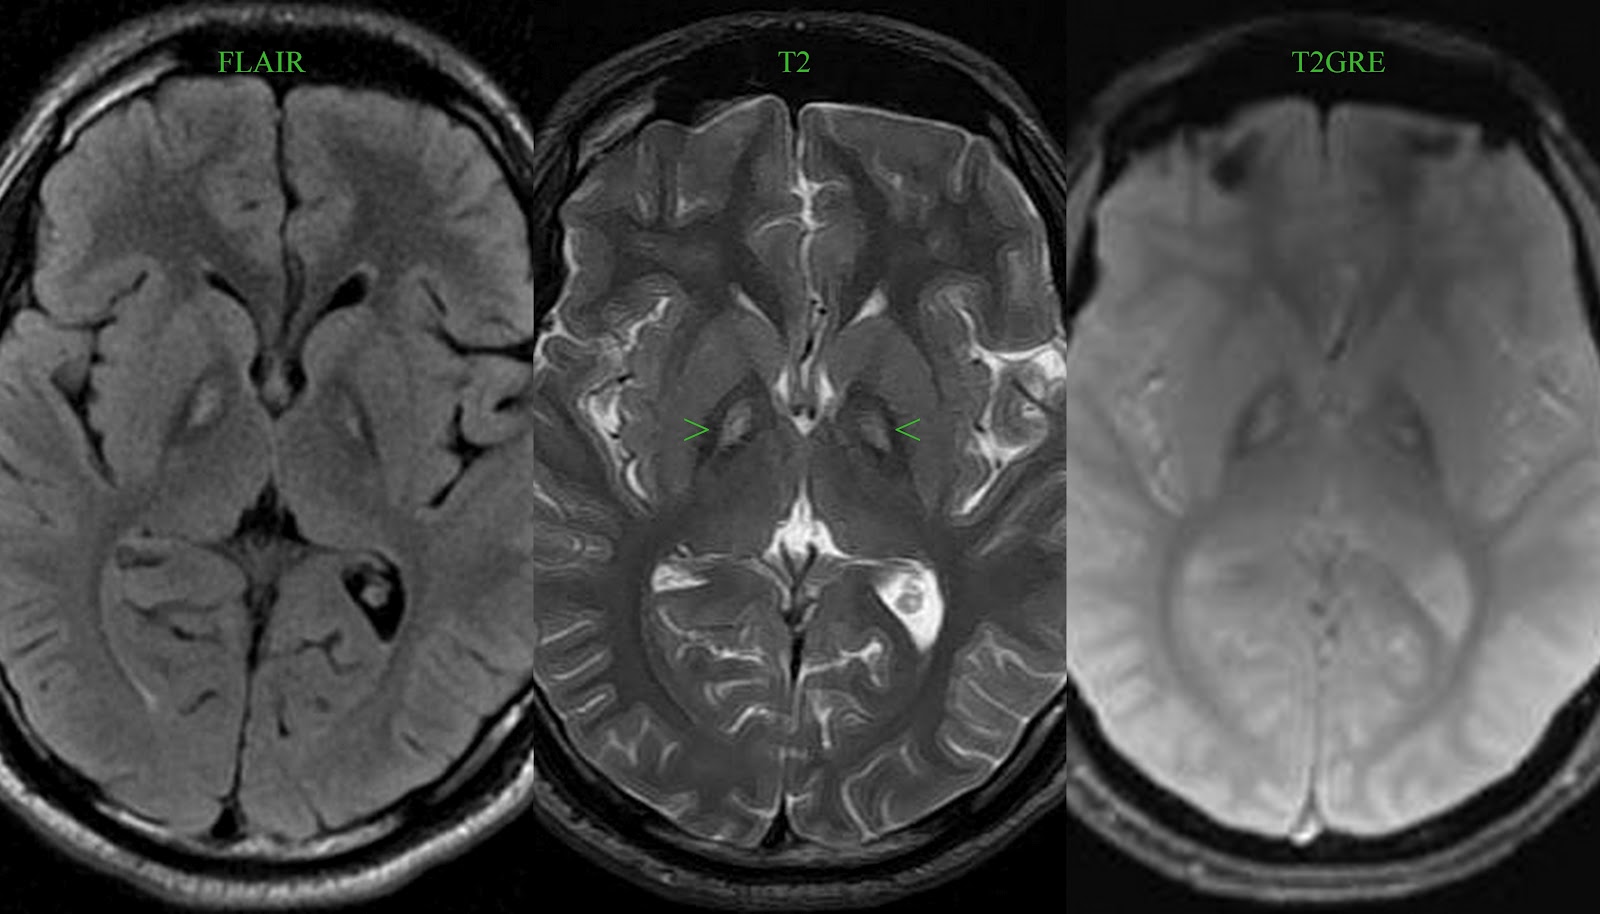

Демиелинизирующие заболевания мозга: МРТ изображения